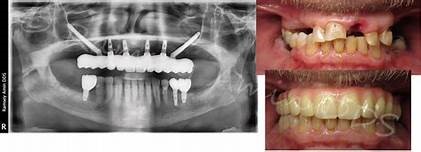

All-on-4 Dental Implants:

All-on-4 dental implants are an advanced full-mouth restoration solution designed for patients missing most or all of their teeth. This treatment uses four strategically placed titanium implants to support a complete set of fixed, natural-looking teeth. All-on-4 implants provide excellent stability, improved chewing ability, and enhanced smile aesthetics while reducing the need for multiple implants or bone grafting procedures. The treatment offers faster recovery and immediate smile transformation for many patients. All-on-4 dental implants are a long-lasting, comfortable, and reliable solution that restores confidence, speech, facial appearance, and overall oral function with natural-looking results.

Full mouth dental implants are a complete smile restoration solution for patients who have lost most or all of their teeth. This advanced treatment replaces missing teeth with a full set of fixed, natural-looking teeth supported by dental implants. Full mouth implants restore chewing ability, speech clarity, facial aesthetics, and overall confidence while providing superior comfort and stability compared to traditional dentures. The implants help preserve jawbone structure and prevent facial sagging caused by tooth loss. With advanced digital implant technology and precision planning, full mouth dental implants offer a long-lasting, secure, and life-changing solution for a healthy and confident smile.